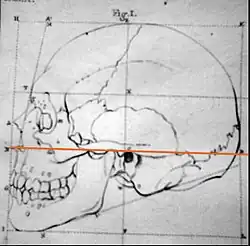

Campersche Ebene (orange Linie)

Campersche Ebene (orange Linie) -

Frankfurter Horizontale (grüne Linie)

Frankfurter Horizontale (grüne Linie) -